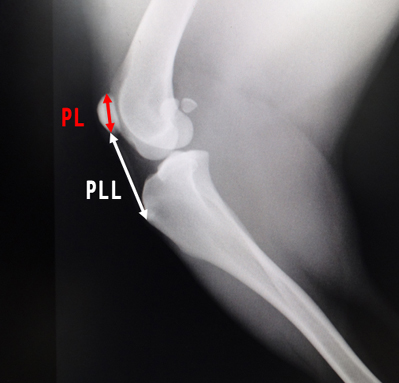

膝蓋骨が高い位置にある場合にX線検査による測定式が存在する。

- 膝蓋骨の長さ(PL)

- 膝蓋靭帯の長さ(PLL)

- PLL/PL比の計算をする、PLL/PL>1.97

- 犬 (小型犬)

正常・・1.7(平均)

MPL・・1.87 (平均)

Alta・・1.87(平均)

参考程度:中・大型犬では2.06以上は内方脱臼のリスクが増加